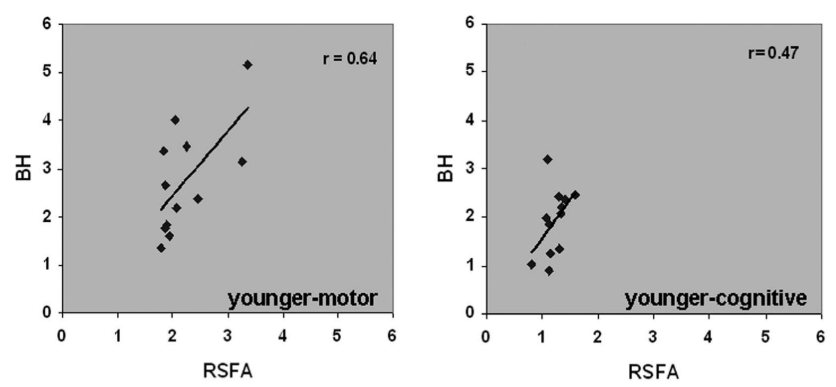

An alternative estimation of CVR (?)

2. Golestani et al. 2016 (NeuroImage)

Estimating CVR with a BH task requires compliant subjects and

dedicated equipment, making it harder to adopt in clinical practice

As a cheaper and feasible alternative, previous literature suggests to use

Resting State fluctuations measures (RSF), such as:

- Resting State Fluctuations Amplitude (RSFA)¹

- [fractional] Amplitude of Low Frequency Fluctuations ([f]ALFF)²

1. Kannurpatti et al. 2014 (PloS ONE)

Results: CVR and RSF

Physiology and RSF

We used 3dLMEr¹ to set up the following LME models (R syntax):

Effect of Sex

Only sex had a significant effect on RSF

Effect on CVR

Results: CVR and RSF

Golestani et al. 2016 (NeuroImage)

Results: CVR, RSF, and tasks

The relationship between CVR, RS fluctuations, and tIA

might be highly subject specific

or absent altogether.

- We did not observe a statistically significant effect of CVR on RS fluctuations, or of CVR and RS fluctuations on task induced activity, most probably due to the high variability between subjects

-

The failure of generalisation of previous observations might be related to different methods, but whether this is related to a better denoising and signal quality or to a possibly non optimal setting (e.g. compared to gas challenges) is uncertain

-

A different statistical perspective (i.e. Bayesian) is required to exclude any relationship between CVR and RS fluctuations, and further analyses are required to improve the agreement between CVR and RS fluctuations